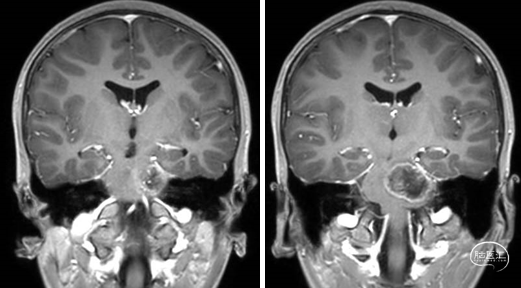

术前MRI

术后MRI